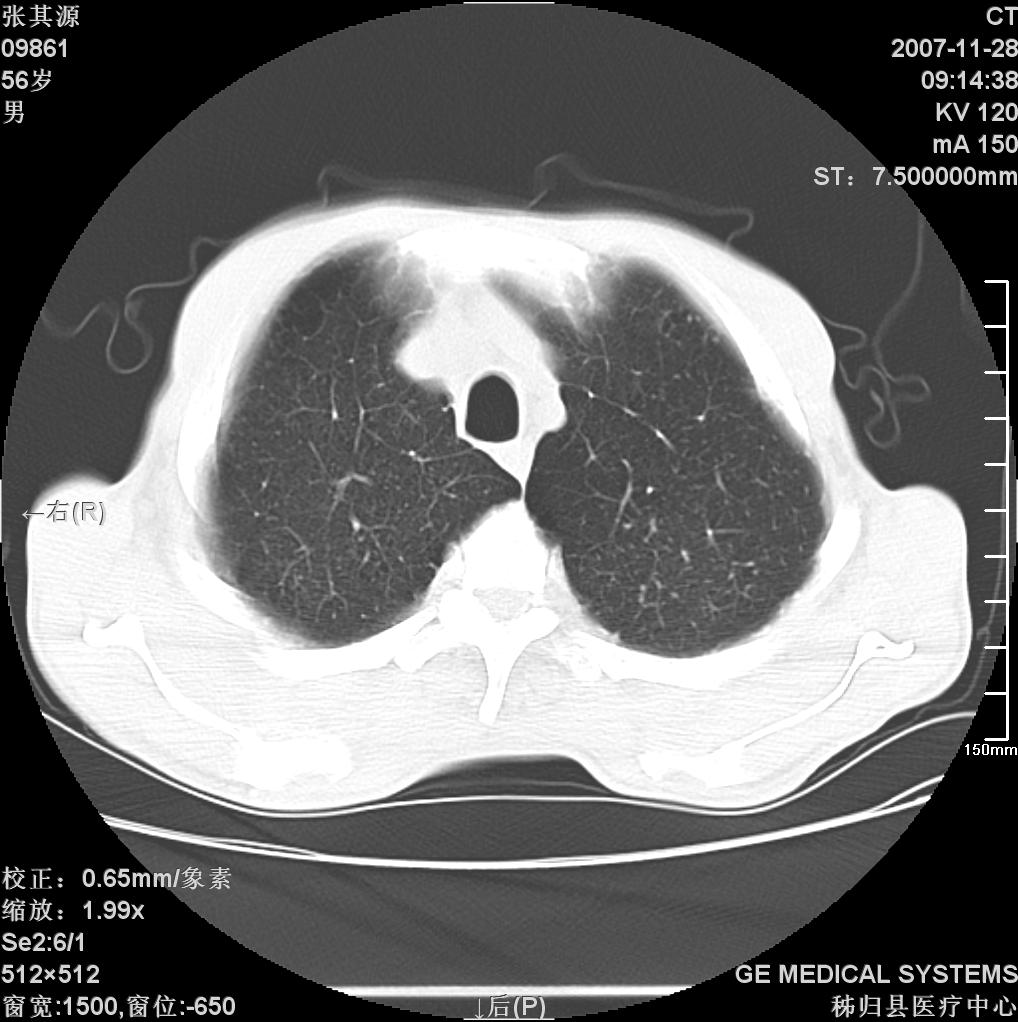

患者因阻塞性黄疸入院,发病前10天持续中等程度发烧.术前检查发现两肺弥漫性病变,请各位大虾会诊,除了考虑急性血源性肺结核外,还有其他什么疾病可能.

影像符合粟粒型肺tb改变。

考虑tb不排除转移,(隆突处有肿大淋巴结,不好说是结核还是转移引起的)

双肺多发粟粒样病灶,右肺胸膜下结节样病灶,气管前腔静脉后及隆突下均见肿大淋巴结,结合胆道肿瘤病史首先考虑转移。另外心影密度略低,时间格显示,是否有贫血?查明白再手术吧!